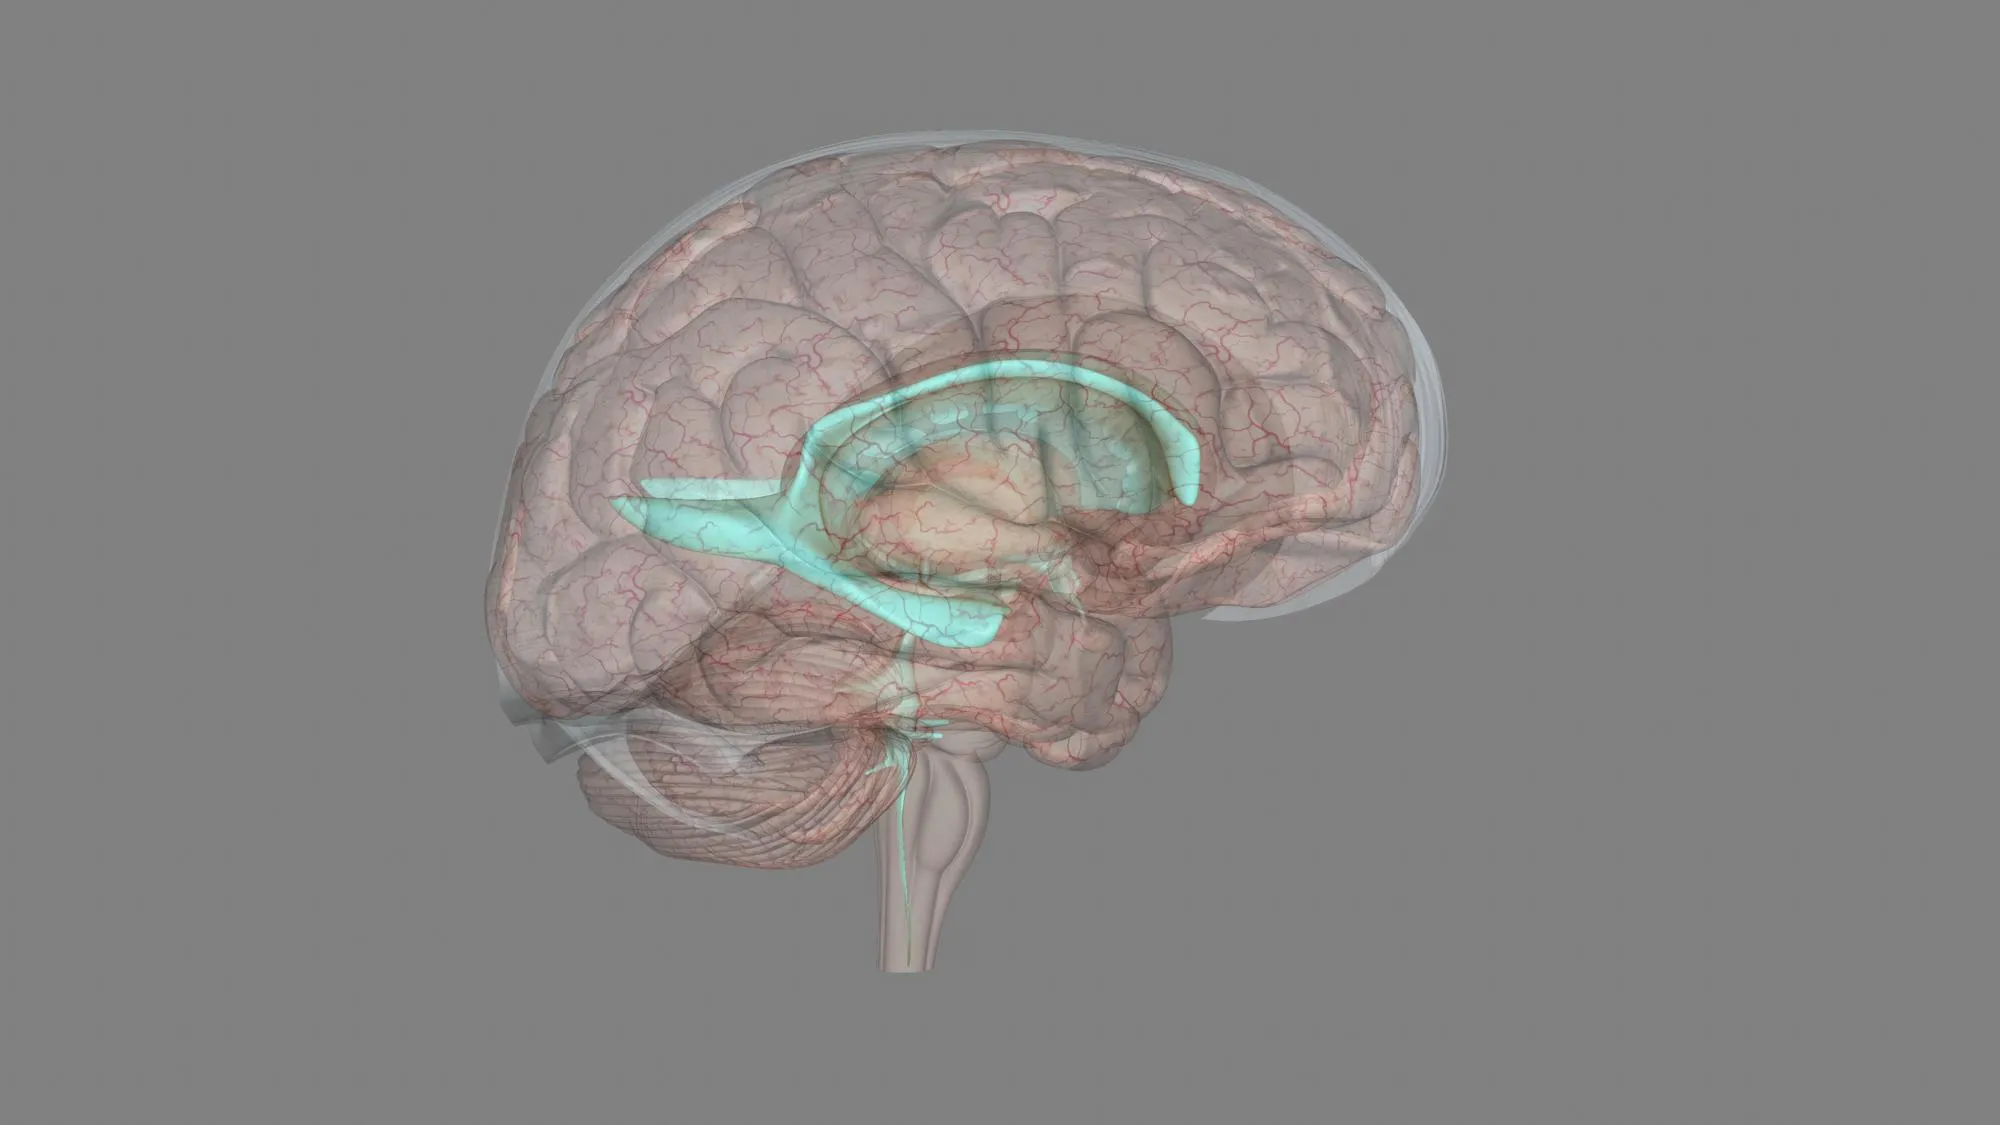

Diagnostic imaging was pivotal in identifying the exact cause of the recorded symptoms. Computerized tomography (CT) and magnetic resonance (MR) imaging revealed a small defect in the clival bone. This defect provided a pathway for the CSF to leak and subsequently become an entry point for pathogens leading to repeated infections. It is within this investigative context that the chordoma—a rare type of bone cancer—was diagnosed. The endoscopic transnasal repair was performed successfully, addressing the CSF leakage.

The occurrence of a chordoma presenting as recurrent bacterial meningitis with CSF leakage is rare, to the point of being nearly unheard of in general clinical practice. However, this case emphasizes the need for healthcare professionals to be aware of such possibilities. It also exhibits the fundamental role that imaging techniques such as CT, MR, and MR cisternography play in unlatching the causes of cryptogenic infections.